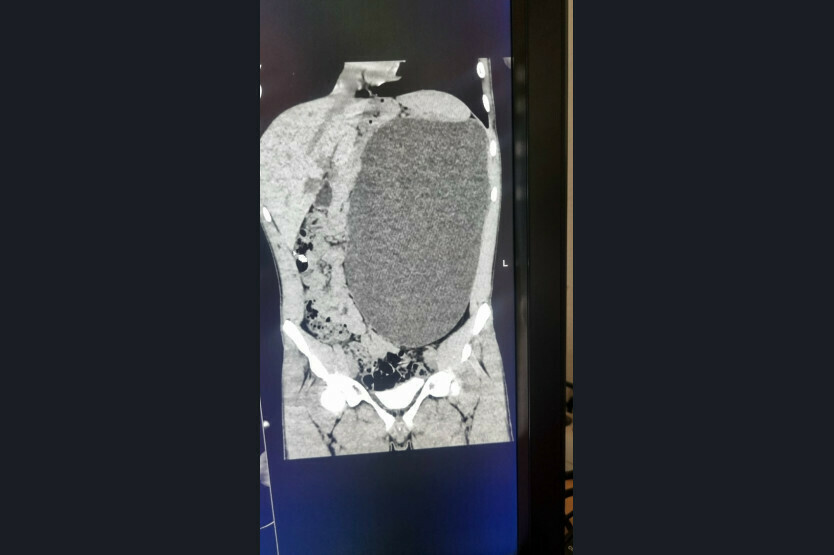

«Это была случайная находка. Парень к нам поступил из амбулаторного звена. Он устраивался на работу. Ему перед трудоустройством сделали УЗИ, нашли объемное образование в брюшной полости. Мы стали обследовать, оказалось, что это гидронефроз левой почки с отсутствием паренхимы (основная ткань органа, выполняющая его функции – Прим. ред.)», – отметила детский хирург-уролог Ирина Живолуп.

Гидронефроз – это заболевание почки, которое характеризуется стойким нарастающим расширением ее полостей, атрофией почечной паренхимы в результате нарушения циркуляции крови и оттока мочи из почки. Эта патология приводит к повышению внутрилоханочного давления и повреждению почечной ткани. Часто гидронефроз длительное время протекает бессимптомно и обнаруживается случайно при ультразвуковом обследовании.

«У нашего пациента почка достигла размеров пятилитровой бутылки! Она занимала почти весь объем живота и давила на все соседние органы. Это была настоящая бомба замедленного действия: любая травма, случайный удар в живот – и мешок мог разорваться внутри», – рассказали в ДГКБ № 1.